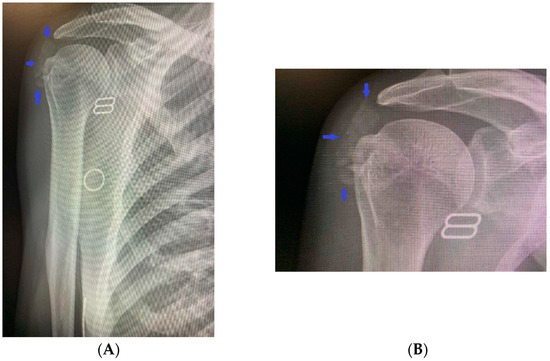

Additionally, there was functional, palpable discomfort, along with movement limitations. The general physical status did not show any pathological abnormalities. Biochemical tests confirmed the previous findings of disturbances in the phosphorus metabolism of the patient: hyperphosphatemia (2.27 mmol/L, normal range 0.77–1.36 mmol/L), reduced 24 h urinary excretion (9.2 mmol/L, normal range 10.9–32.3 mmol/L), low 24 h phosphate clearance (0.08 mL/s, normal range 0.140–0.151 mL/s), increased tubular reabsorption (94.1%), and normal levels of total calcium (2.41 mmol/L, normal range 2.15–2.5 mmol/L) and ionized calcium (1.28 mmol/L, normal range 1.16–1.31 mmol/L), 24 h urinary excretion (3.7 mmol/L, normal range 2.5–7.5 mmol/L), 1.25 (OH) vitamin D3 (57 ng/mL, recommended levels above 50 ng/mL), and parathyroid hormone (31.1 pg/mL, normal range 12–88 pg/mL). An X-ray of the shoulder joint showed calcium deposits in the surrounding soft tissues (Figure 2A,B).

Figure 2.

(A,B) An X-ray of the right shoulder joint revealing calcium deposits in the surrounding soft tissues.